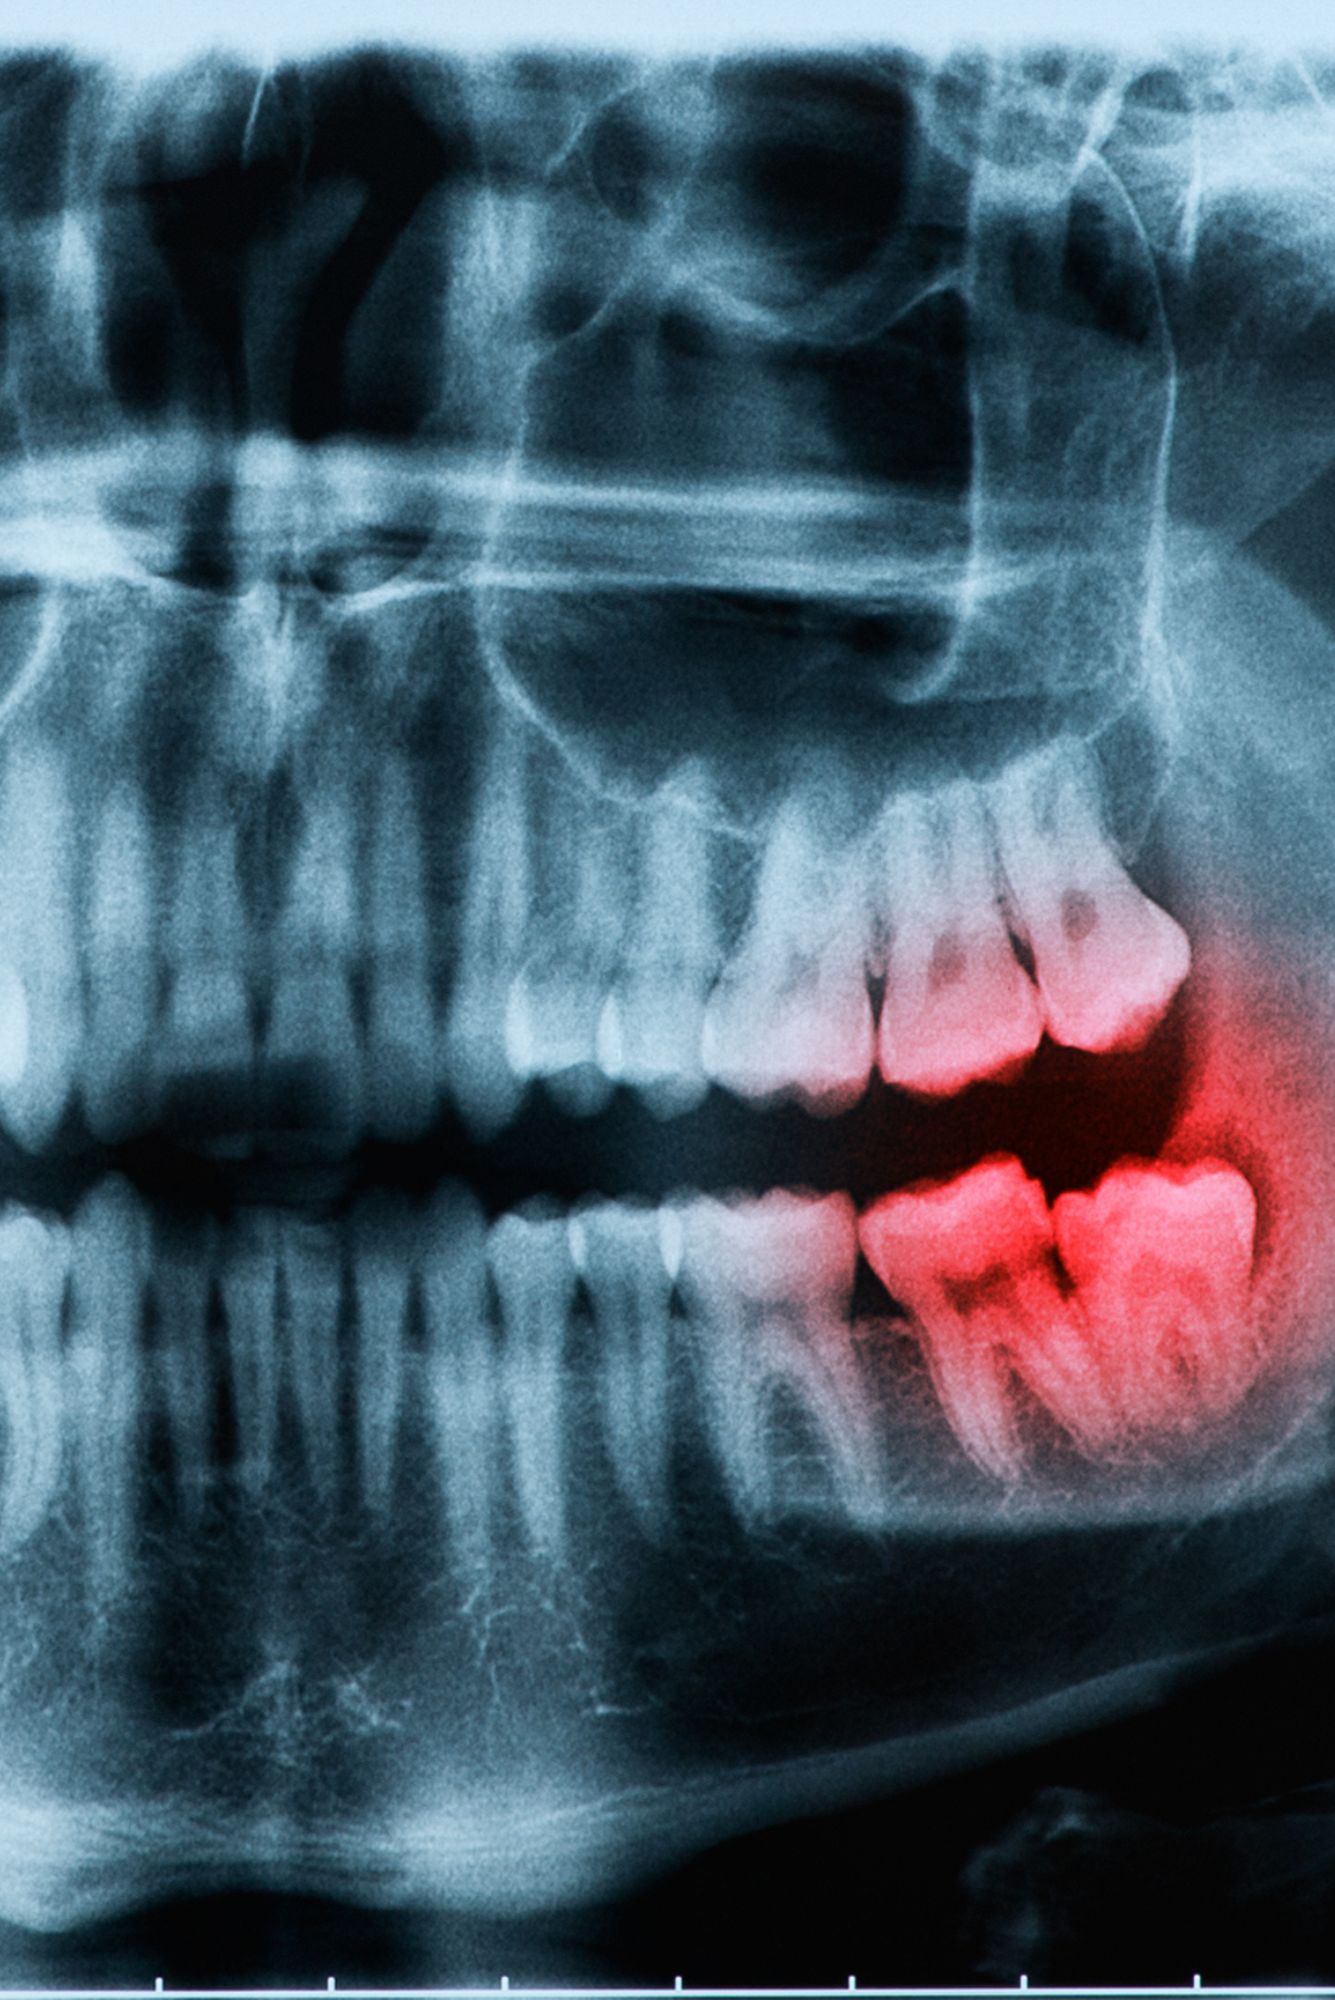

Les dents de sagesse sont les dents les plus éloignées dans les arcades dentaires et refusent parfois d’émerger lorsqu’elles n’ont pas l’espace suffisant. Or, la majorité des gens ont une mâchoire trop étroite pour accueillir une dentition complète.

Dans ce cas de figure, les dents de sagesse risquent de demeurer incluses. Par ailleurs, si celles-ci tardent trop à percer, elles risquent fortement d’être semi-incluses (croissance inachevée). La majorité des professionnels dentaires estiment que les dents de sagesse problématiques devraient être extraites.

L’extraction permet alors d’éviter des complications telles que la douleur, une infection ou l’entassement des dents voisines.